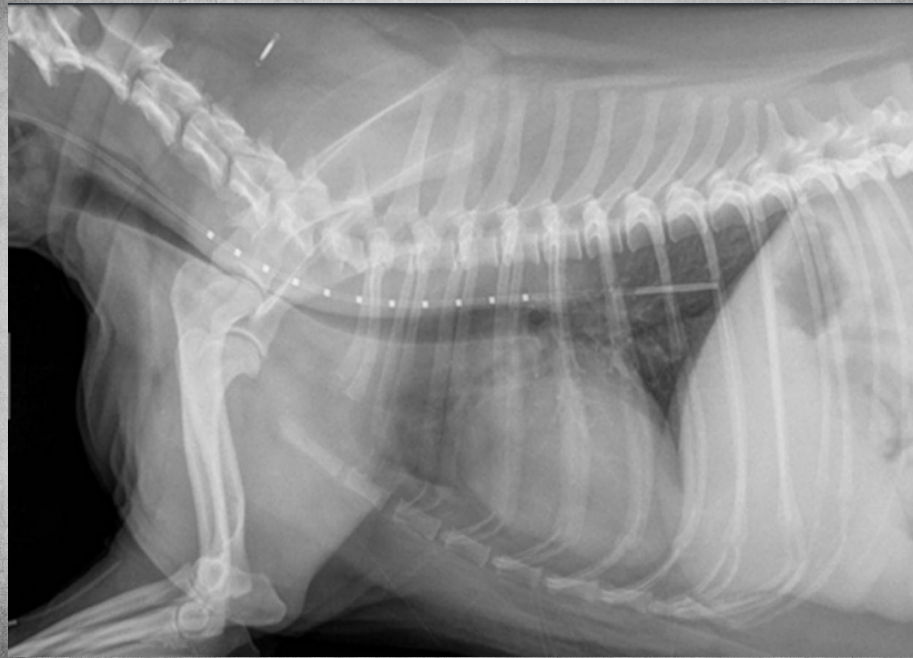

● 12 yo male castrated Shih-Tzu

● Geriatric check-up

● No clinical signs

congenital peritoneal-pericardial diaphragmatic hernia

these intestines are filled with gas due to

being empty

gastric axis also altered